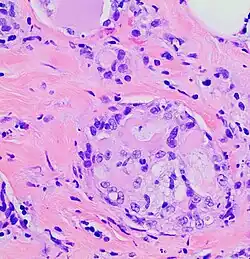

In 1980, Tavaosoli and Norris renamed juvenile breast carcinoma as "secretory carcinoma of the breast" based on its characteristic microscopic appearance[7] of having eosinophilic (i.e. red or pink) extracellular secretions when its tissues were stained with the H&E stain.[8] MSC has sometimes been termed secretory carcinoma without reference to its breast cancer location. However, the term secretory carcinoma has also been used to name tumors with the microscopic appearance of MSC that are localized in the salivary glands (now termed mammary analogue secretory carcinoma),[9] thyroid gland (now termed salivary gland–type carcinoma of the thyroid),[10] or skin (now termed secretory carcinoma of the skin or primary cutaneous mammary analog secretory carcinoma).[11][12] Mammary secretory carcinoma is used here to distinguish it from these formerly termed secretory carcinomas.

The microscopic histopathology of H&E-stained MSC tumors generally shows well-circumscribed solid tumors with multiple microcysts[13] and sheets of epithelial cells containing numerous vacuoles in their cytoplasm, signet ring cells (i.e. cells with one large cytoplasmic vacuole termed a globule), and extracellular droplet-like secretions resembling the cytoplasmic globules.[2] The sheets of cells are separated by bands of connective tissue.[5] In occasional cases, the cells in MSC tumors are arranged in a papillary (i.e. finger-like)[17] or tubular[14] pattern. The extracellular microcysts and intracellular vacuoles and globules stain red when stained with the H&E stain, consist of sulfated glycosaminoglycans and mucin-containing material,[4] and are identified using periodic acid-Shiff, PAD diastase, or Alician blue stains.[15] The term “secretory” for MSC is in recognition that the tumor cells vacuoles and globules are secreted extracellularly to give the tissues their microcystic appearance.[8] At least 2 cases of MSC had sarcoma-like malignant cells in portions of their tumors and a rapidly metastasizing disease.[18][19]